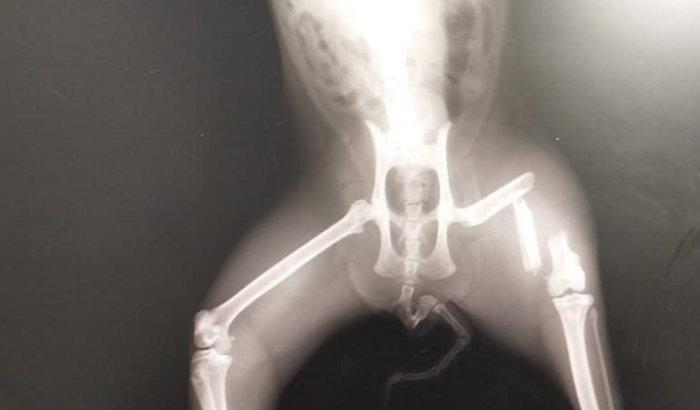

Olá pessoal, preciso da ajuda de todos vocês, me mudei recentemente e infelizmente minha gata acabou fugindo… ela é castrada e nunca tinha saído antes.Quando minha gata voltou pra casa já percebi que não estava bem, não sei se ela foi espancada ou atropelada, mas quebrou a perna, de imediato corri com ela para o veterinário para saber a gravidade do ocorrido e infelizmente ela terá q fazer uma cirurgia que ficou em 3.470, eu estou grávida, ainda não tenho as coisas do bebê e não tenho condições de pagar a cirurgia da minha gata (mia) e minha amiga me deu a ideia de fazer a vaquinha para conseguir ajudar, ela precisa realizar a cirurgia o quanto antes. Desde já agradeço a todos que poderem colaborar 🙏❤️